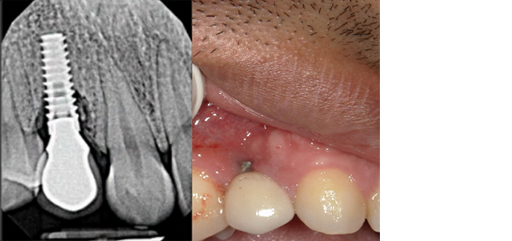

Gingival recession

Gum Disease Treatment

Your gums are the foundation of your smile and overall health. We’ll show you what we see, explain the next steps, and treat your gums with state-of-the-art techniques. Dr. Jang is a skilled periodontist who’s here to keep your smile strong for the long term.